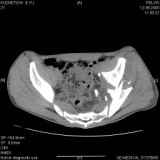

Уважаемые коллеги! Хотелось бы услышать совет по тактике лечения представлленого больного.Поступил после лечения в одном изотделений области. Травма 2,5 месяца назад. После выведенияиз шока был произведен остеосинтез перелома бедра, предплечья, до перевода к нам проводилосьвытяжение по оси шейки бедра за стержень, введенный в большой вертел. На сегодня деформацияригидна, клинически мобильности не определяется. Заранее признателен. P.S. Данный вид травм не включен в перечень "высокотехнологичных операций", направить длялечения по квотам Минздрава очень сложно.

Привет, Леонид. Оскольчатый высокий двухколонный перелом в такие сроки трогать не надо, т.к. это про такие переломы сказано: "кто с ножом на Ж. пойдет тот в ней и останется...".